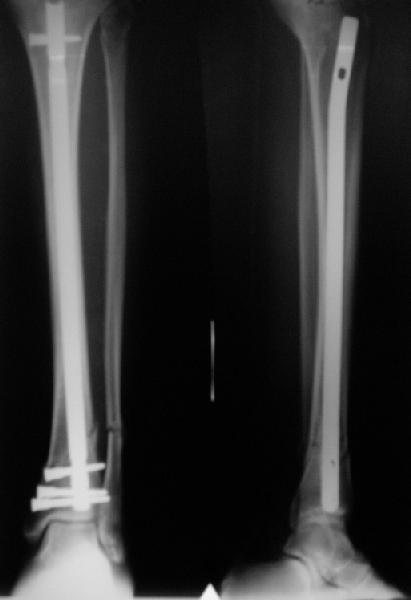

A typical case is attached, also an image with intra-op reduction obtained by a small wire distractor, in the moment of insertion a Poller wire in AP direction. Fixation by a SIGN nail. Despite the fibula was not fixed healing was obtained with the unchanged alignment.

At least both the ankle mortise and tibial alignment look acceptable, don't they?

I am just trying to illustrate that prevention of 1)tibial valgus and 2)loss of reduction can be provided without fibular plating. Small changes of conventional nailing techniques allow to maintain reduction of the tibia reliably without adjunctive fibular stabilization.